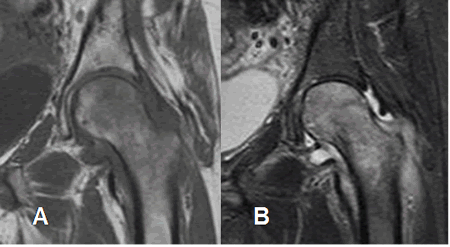

Fig 19. Edema óseo congestivo.

A: RM coronal en T1 y B: RM coronal en STIR. Cabeza y cuello femoral hipointensos en T1 e hiperintensos en STIR por edema óseo, secundario a osteoporosis transitoria.